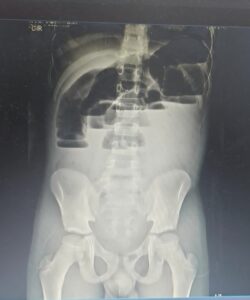

Não apresenta história prévia de dificuldade para evacuar. Ao exame, paciente apresentava distensão abdominal e dor difusa à palpação. Solicitado RX de abdome.

Diante do quadro clínico e achados no exame de imagem, qual a principal hipótese diagnóstica?

BObstrução intestinal de delgado

CMegacólon congênito

DVolvo de sigmóide